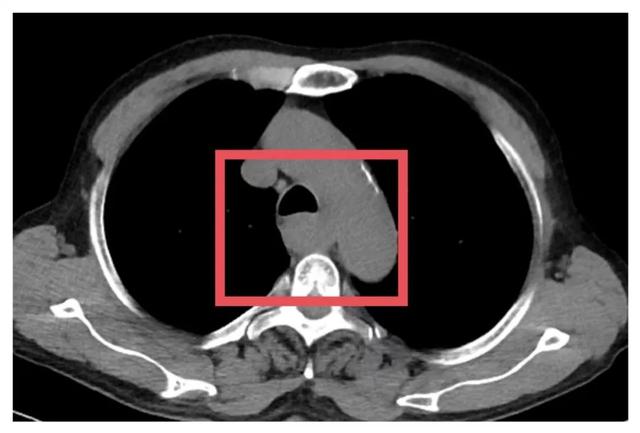

▲患者术前影像学检查

面对肿瘤,不少患者会直观地认为“早点动手术”是最好的选择。但事实上,对于像苏先生这样的局部晚期患者而言,贸然手术可能风险更大,远期疗效也难以保障。

为了争取更大的根治机会,胸外科朱震主任医师为苏先生量身定制定了一套治疗方案——“免疫联合化疗”的新辅助治疗方案,先“软化”肿瘤、减少侵犯,再择期手术。治疗期间,苏先生接受了PD-1单抗与铂类+紫杉醇联合化疗。随着治疗推进,患者主诉症状显著缓解。2025年7月复查CT提示病灶缩小、边界清晰、与周围结构粘连减少,手术时机成熟。